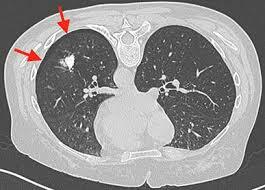

5

Tomografía computarizada

Evalúa la magnitud de la superficie disponible

para el intercambio gaseoso y el potencial de reclutamiento alveolar.

Según los expertos, la TAC aún debe considerarse el estándar de oro para la investigación pero no para el uso clínico rutinario.